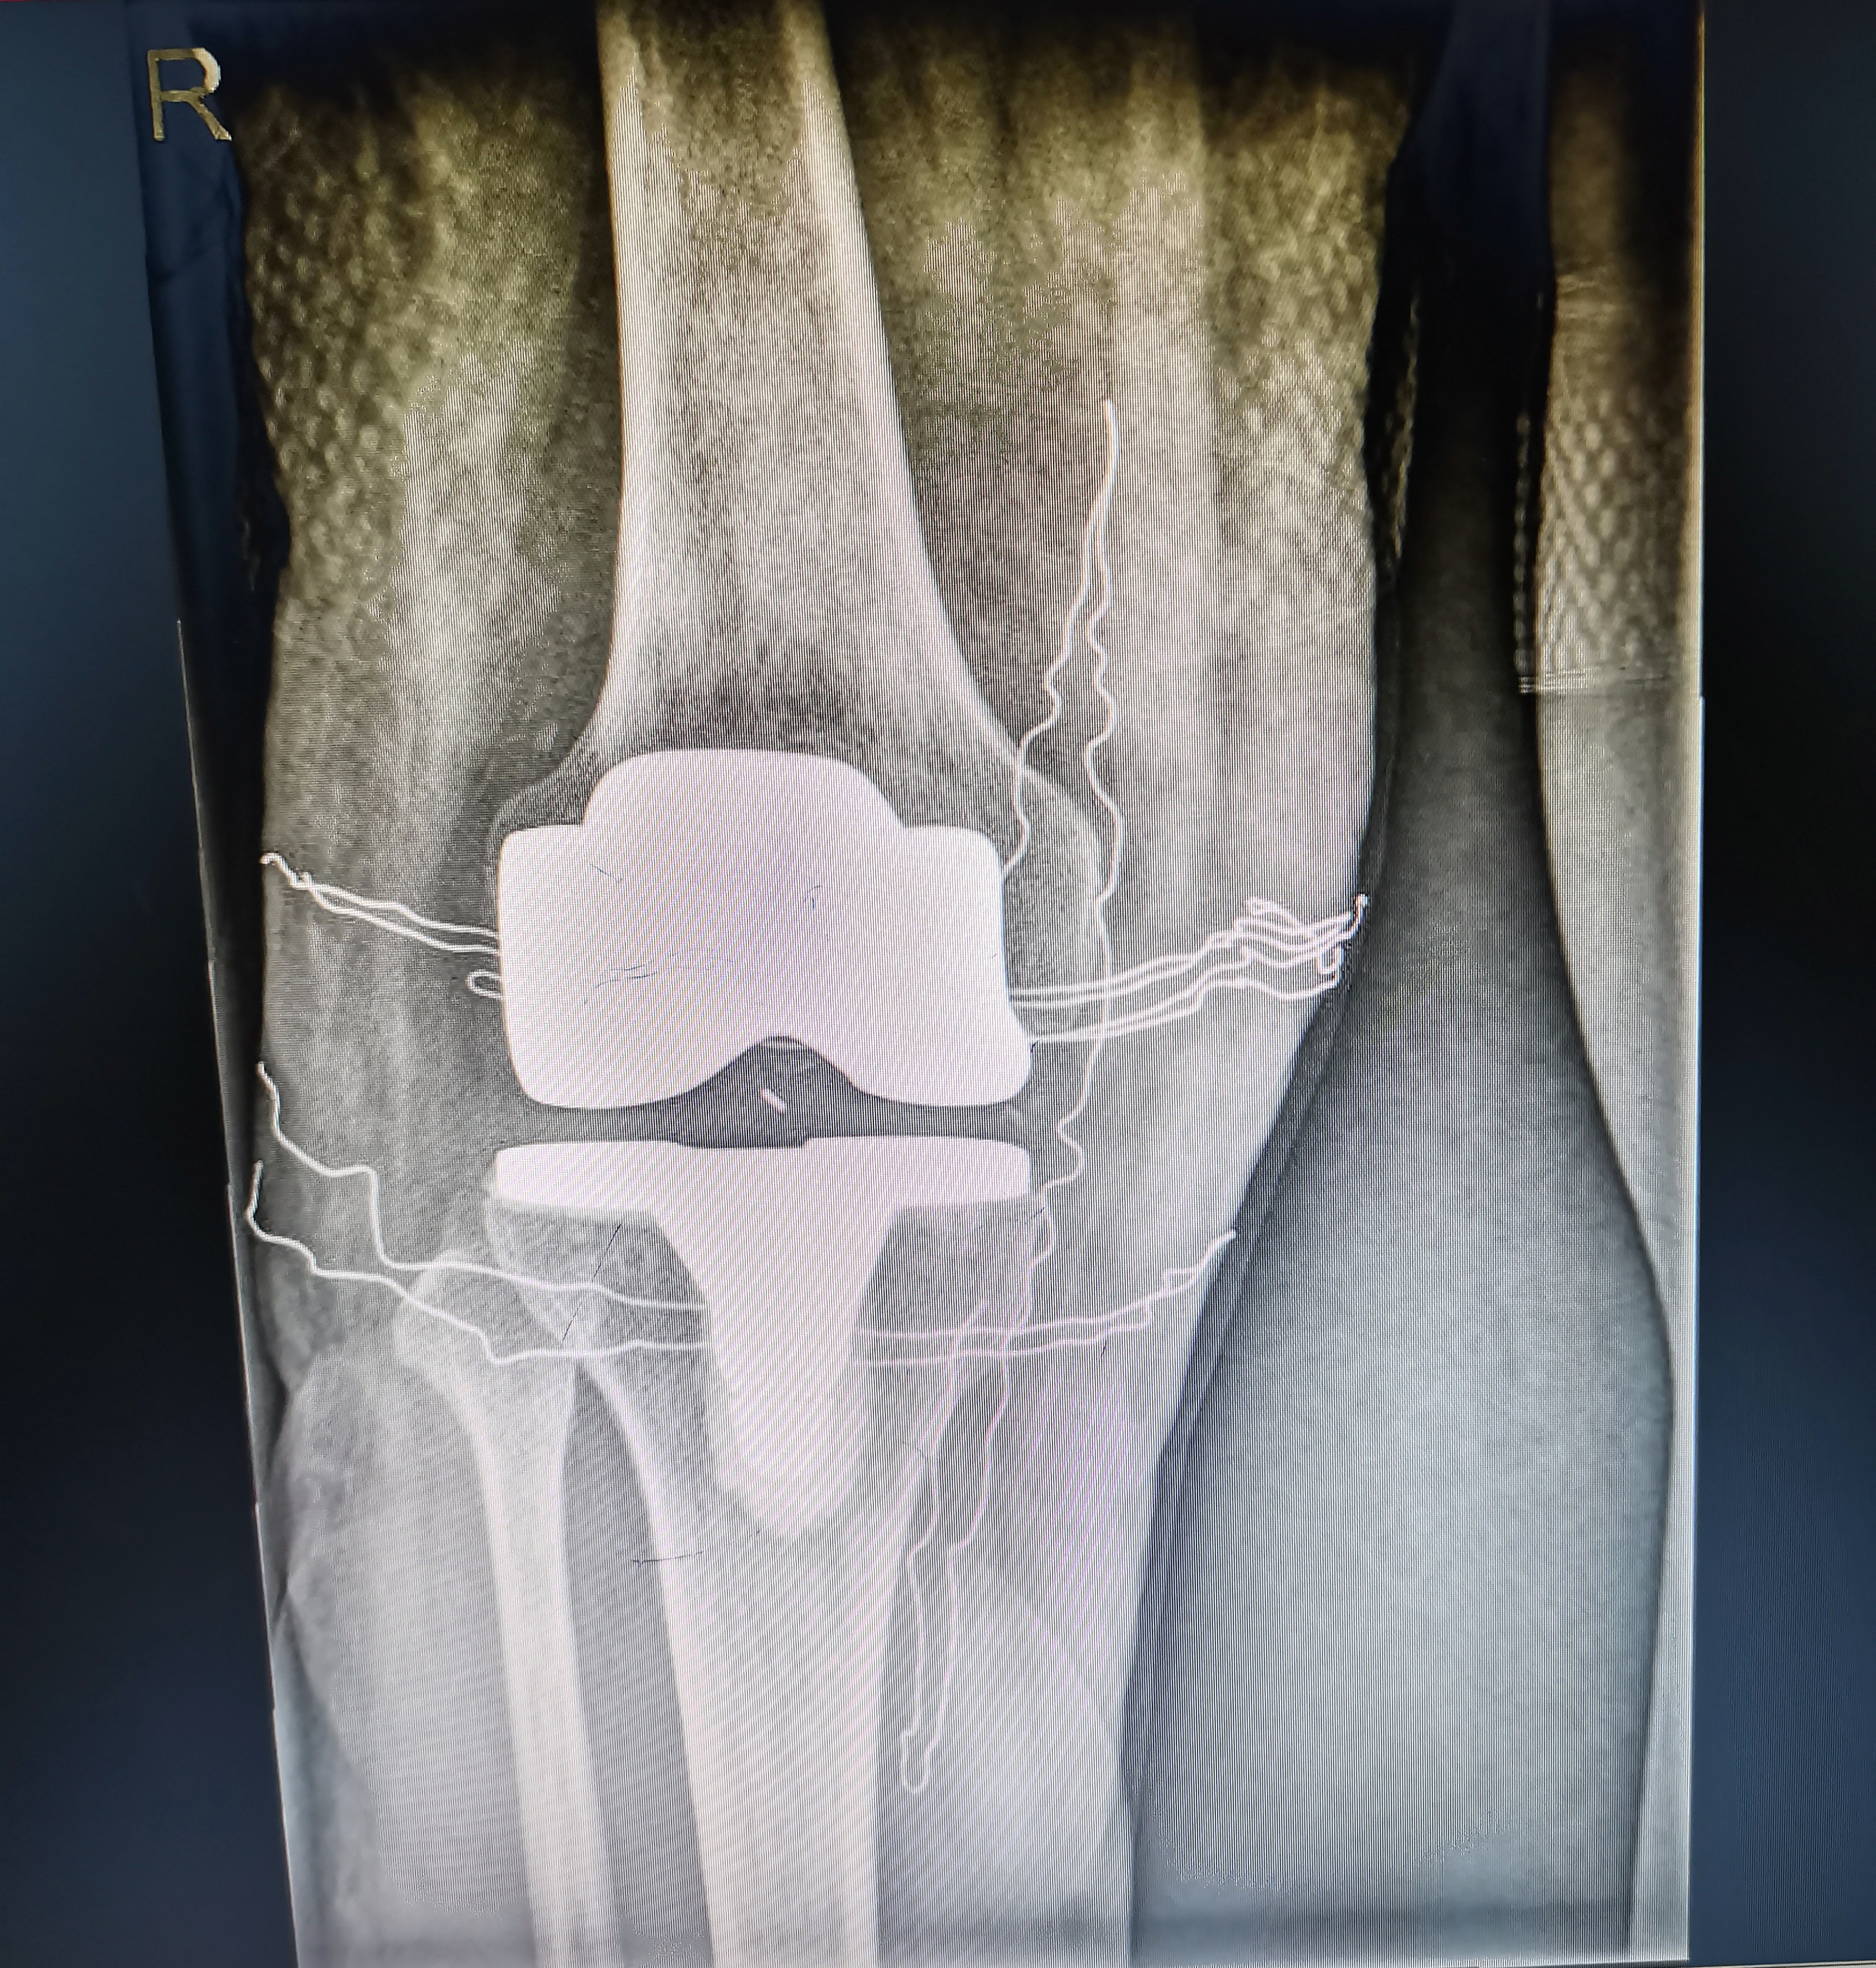

術后照片